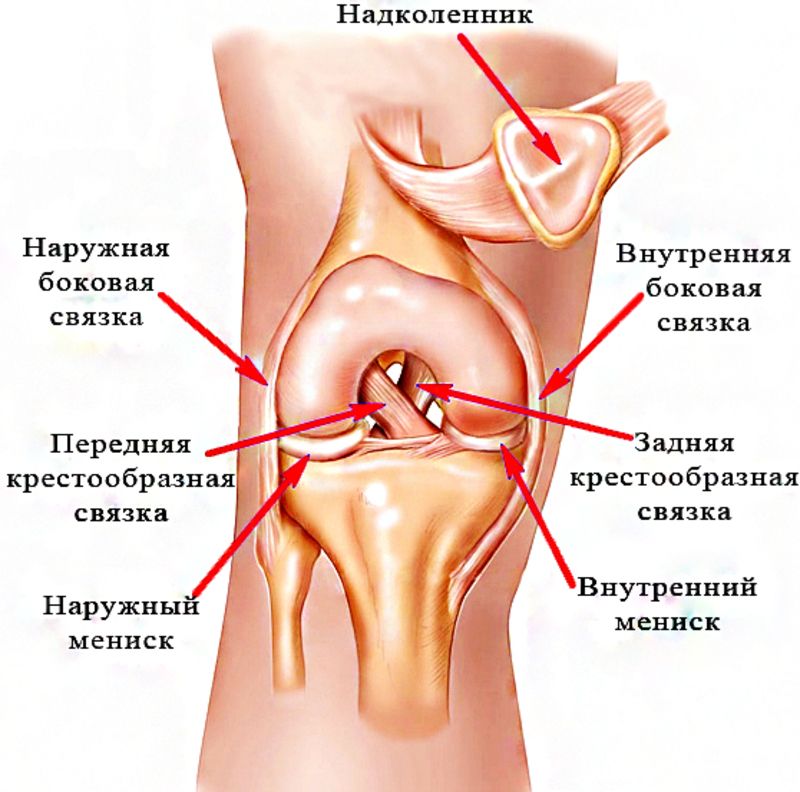

Анатомические изображения менисков и коленного сустава

Раздел: Иллюстрированные советы